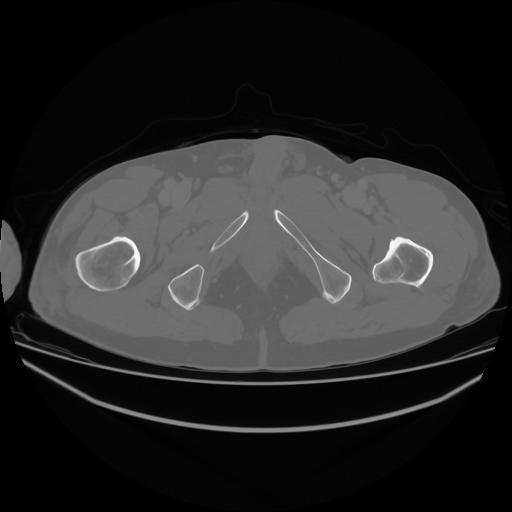

5 CUERPO,CE,Vol,1.0,CUERPO,,